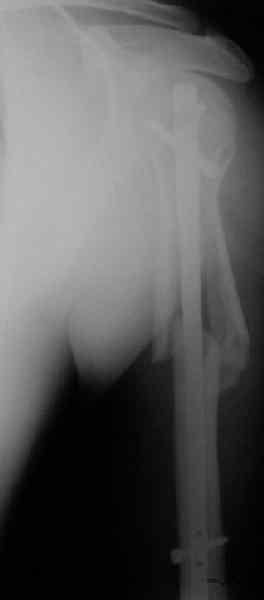

Попытка закрыто изменить положение не удалась. Передним доступом сделали открытую репозицию, гленоид без особенностей. Временно фиксировали спицами и остроконечным костедержателем. Фиксировали гвоздем T2 PHN (Stryker). Для профилактики вывихов после введения проксимальных винтов ротировали дистальный отдел кнаружи на 30

градусов как аналог остеотомии по Weber. Снимки в приложении. Комментарии и критика привествуются.

Attempt of closed reduction failed. Open reduction via anterior approach. The head was temporarily fixed by wires and sharp clamps. Fixation by a nail - T2 PHN (Stryker). The distal fragment has been rotated 30 degrees externally after proximal locking for dislocation prevention as "virtual" Weber osteotomy. Images attached.

Comments/critics are welcome.

I have never used that particular implant.

Is there only a single screw in the head?

To my mind it was most suitable for this injury because of long shaft extension.

> Is there only a single screw in the head?

All 3 screws are in the head. The feature of the nail is that it has four holes oriented not 45 degrees to frontal or sagittal planr, but anatomically to the head and both tubercles. The holes in the nail are threaded so angular stability is perfect, and contain a nylon bushing

preventing any screw rotation/back out.